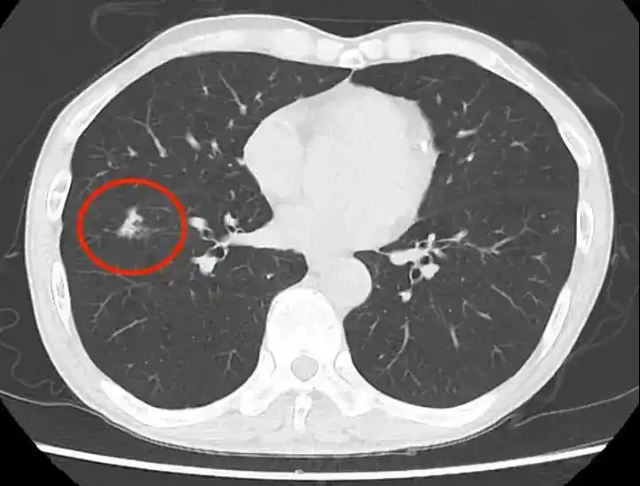

肺结节:肺结节是胸部CT检查中经常发现的一种病变。它表现为肺部的圆形或类圆形结节影,直径一般小于3cm。肺结节的性质多种多样,可以是良性的,如炎性结节、结核球等,也可以是恶性的,如肺癌。对于肺结节的诊断要点,首先要观察结节的大小、形态、边缘特征、内部密度等。较小的结节(小于5mm),如果边缘光滑、密度均匀,多为良性结节,建议定期随访观察。而对于较大的结节(大于8mm),尤其是边缘有毛刺、分叶,内部密度不均匀,或者存在胸膜牵拉征等恶性征象的结节,需要进一步进行增强扫描、PET - CT检查或经皮肺穿刺活检等,以明确其性质。

肺癌:肺癌在胸部CT上的表现因病理类型和分期不同而有所差异。早期肺癌可能表现为肺部的小结节影,随着病情的发展,可出现肿块影,肿块边缘不规则,有毛刺、分叶等征象,内部可有空洞形成,或伴有肺门淋巴结肿大、纵隔淋巴结转移等。对于疑似肺癌的患者,我们需要综合分析CT图像上的各种征象,同时结合患者的吸烟史、家族史、临床症状等因素,进行早期诊断和分期评估,以便制定合理的治疗方案。